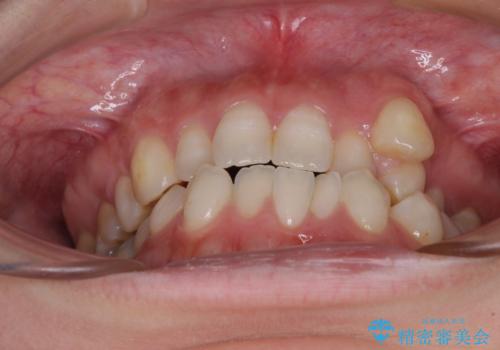

- 左上の八重歯と前歯のデコボコを気にして来院された患者様です。

下顎が左側にズレており、下顎前歯は1歯欠損していたため、左上小臼歯1本を抜歯し、ワイヤー装置にて矯正治療を行うこととしました。

骨格のズレと歯の欠損があったため、仕上がりの調整に時間がかかると思いましたが、舌突出癖の改善や顎間ゴムの装着をしっかりと行ってくださったので、速やかに治療を終えることができました。